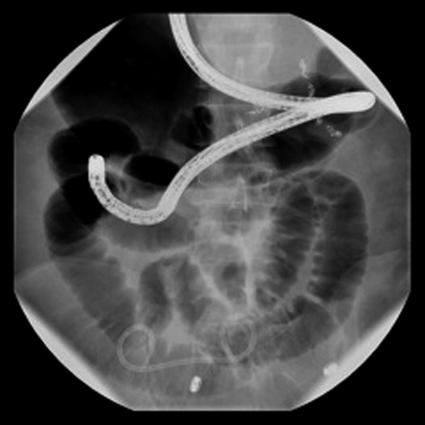

We report the case of a patient who had distal stent migration causing a small bowel obstruction. We successfully retrieved the stent without an enterotomy, by using a combination of laparoscopy, endoscopy, and fluoroscopy. Our unique technique greatly decreased the risk of bacterial peritonitis in this patient with decompensated cirrhosis and associated ascites, which in this patient population results in a high mortality.

我们报告了一例因远端支架移位导致小肠梗阻的患者。我们通过腹腔镜、内镜和荧光镜联合使用,成功地在未进行肠切开术的情况下取出了支架。我们独特的技术极大地降低了该失代偿期肝硬化合并腹水患者发生细菌性腹膜炎的风险,而在这类患者中细菌性腹膜炎会导致高死亡率。